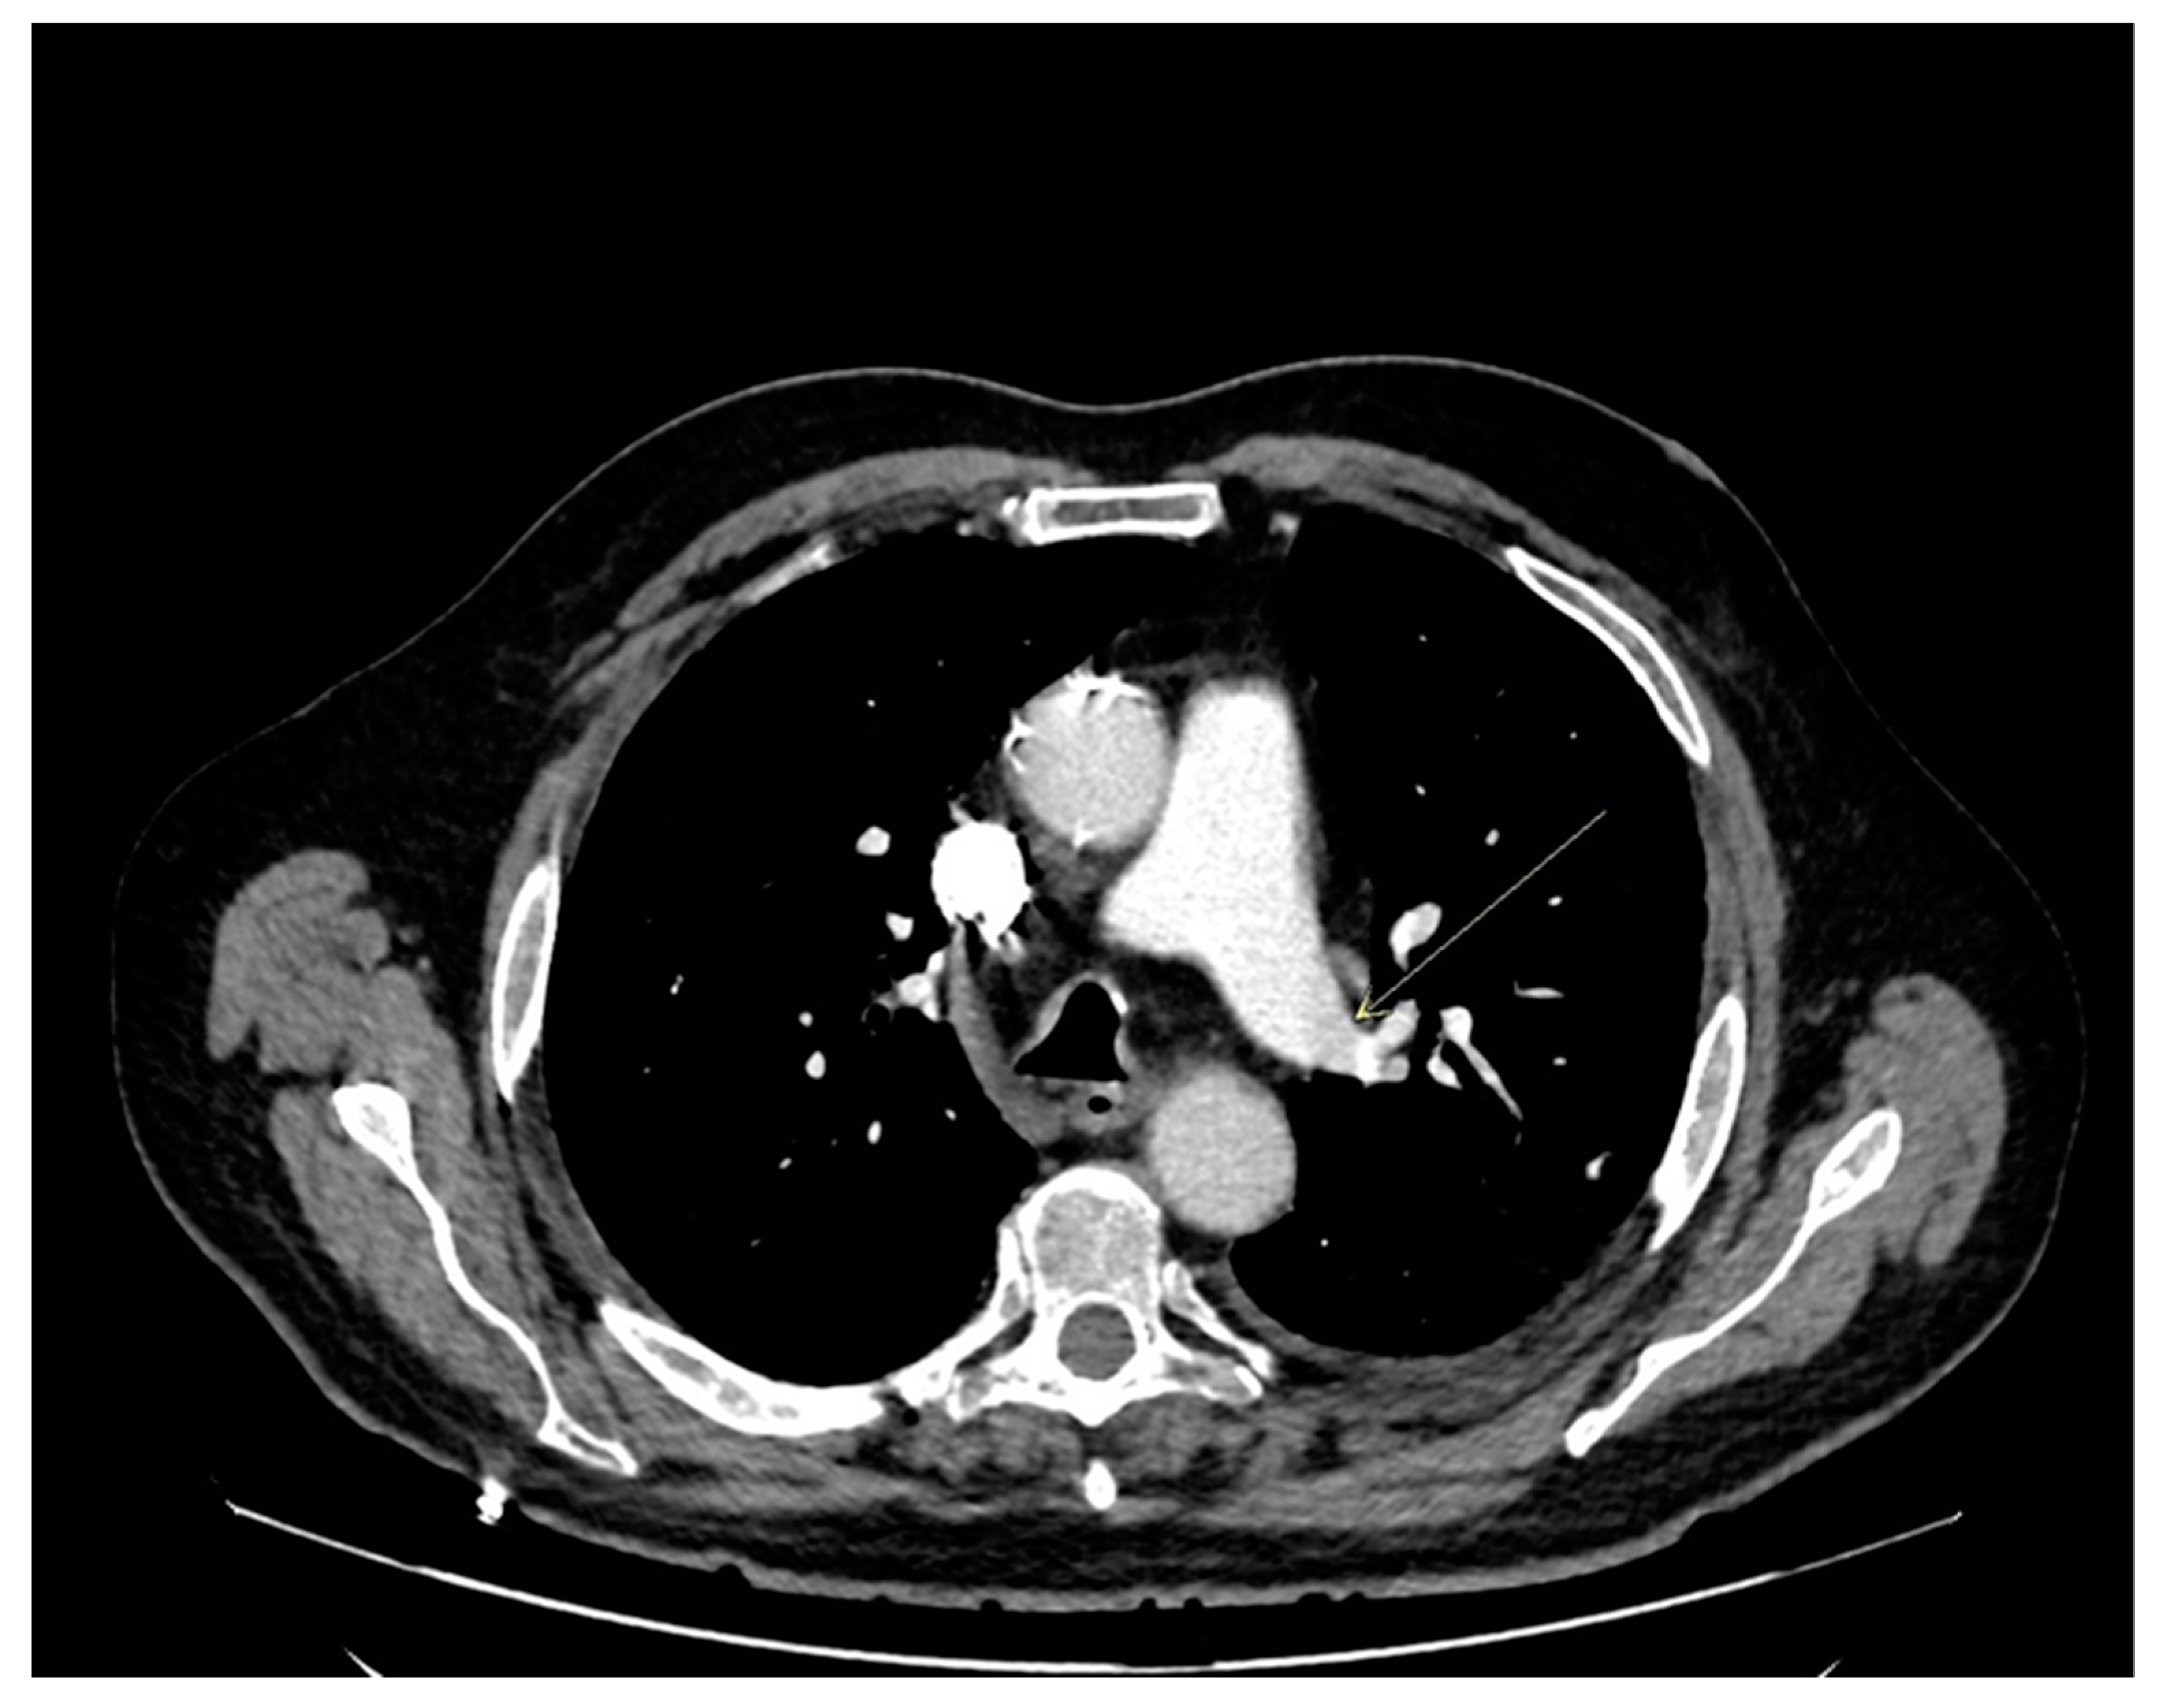

2. Case